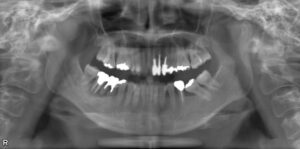

上下臼歯2本欠損症例

BEFORE AFTER 58歳女性/上下2本欠損/インプラント埋込手術 【治療内容】 左上第二小臼歯が欠損状態で、イン…